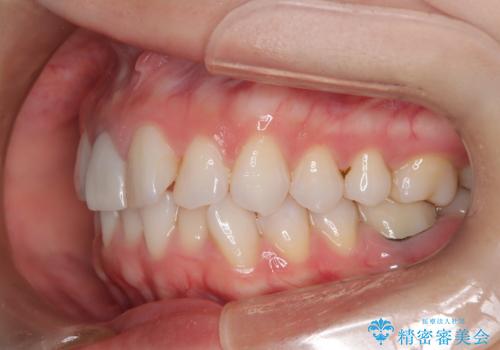

- 前歯のガタつき、変色を主訴に来院された患者様です。術前診査のCT撮影にて、変色した前歯の根の先に病巣があることが判明しました。そこで、マウスピースによる矯正治療と、前歯の根管治療、かぶせ物のやり直し治療を並行して行いました。